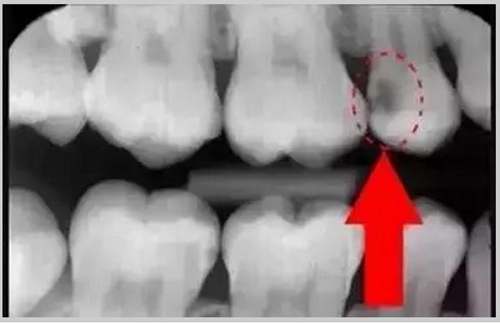

暗的部位說明齲齒已經(jīng)非常嚴重了!

上面這個是接近牙髓了!